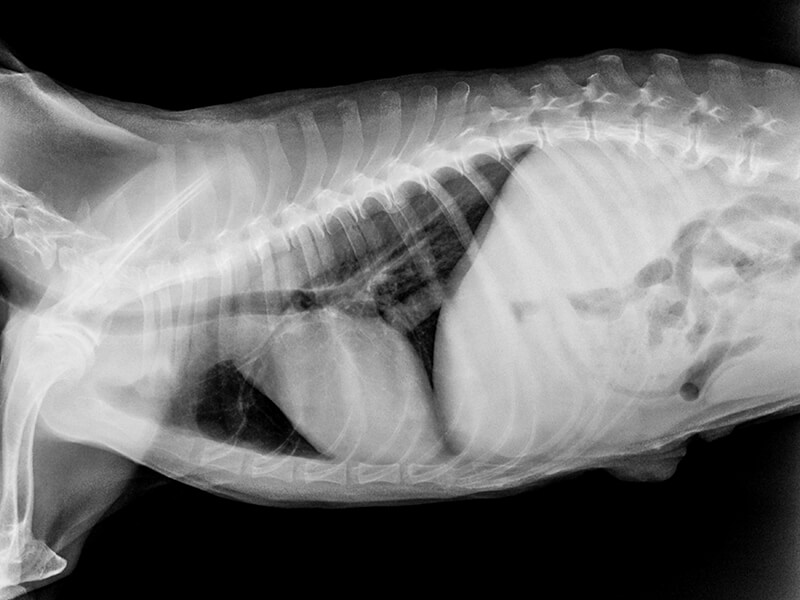

Ακτινολογικό

Το ακτινολογικό τμήμα παρέχει τη δυνατότητα λήψης ακτινογραφιών υψηλής ευκρίνειας, με μηχάνημα τελευταίας τεχνολογίας και μέγιστης ακτινοπροστασίας. Είναι ειδικά σχεδιασμένο για τα κατοικίδια ζώα και η εμφάνιση των λήψεων γίνεται άμεσα σε ψηφιακή μορφή.